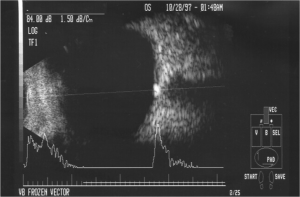

- B-Scan (see below) and A-scan ultrasonography

- B-/A-scan ultrasonography: optic nerve head with ODD is elevated and highly reflective. When decreasing the gain setting, calcified drusen maintain high signal intensity, whereas with papilladema, the signal intensity decreases.